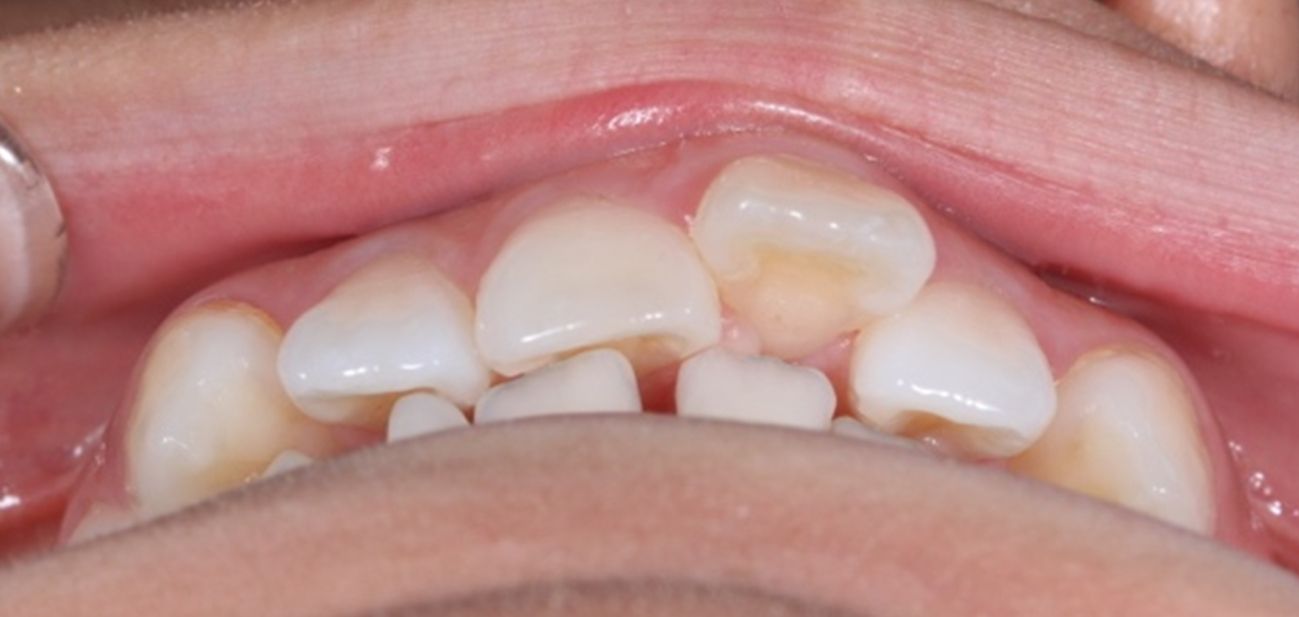

A continuación, mostramos el caso de una paciente adulta con clase II ósea y dentaria.

Con Ortodoncia Invisible, y gracias a la cooperación de la paciente, conseguimos este resultado y, lo más importante de todo, que la paciente sonría sin complejos.